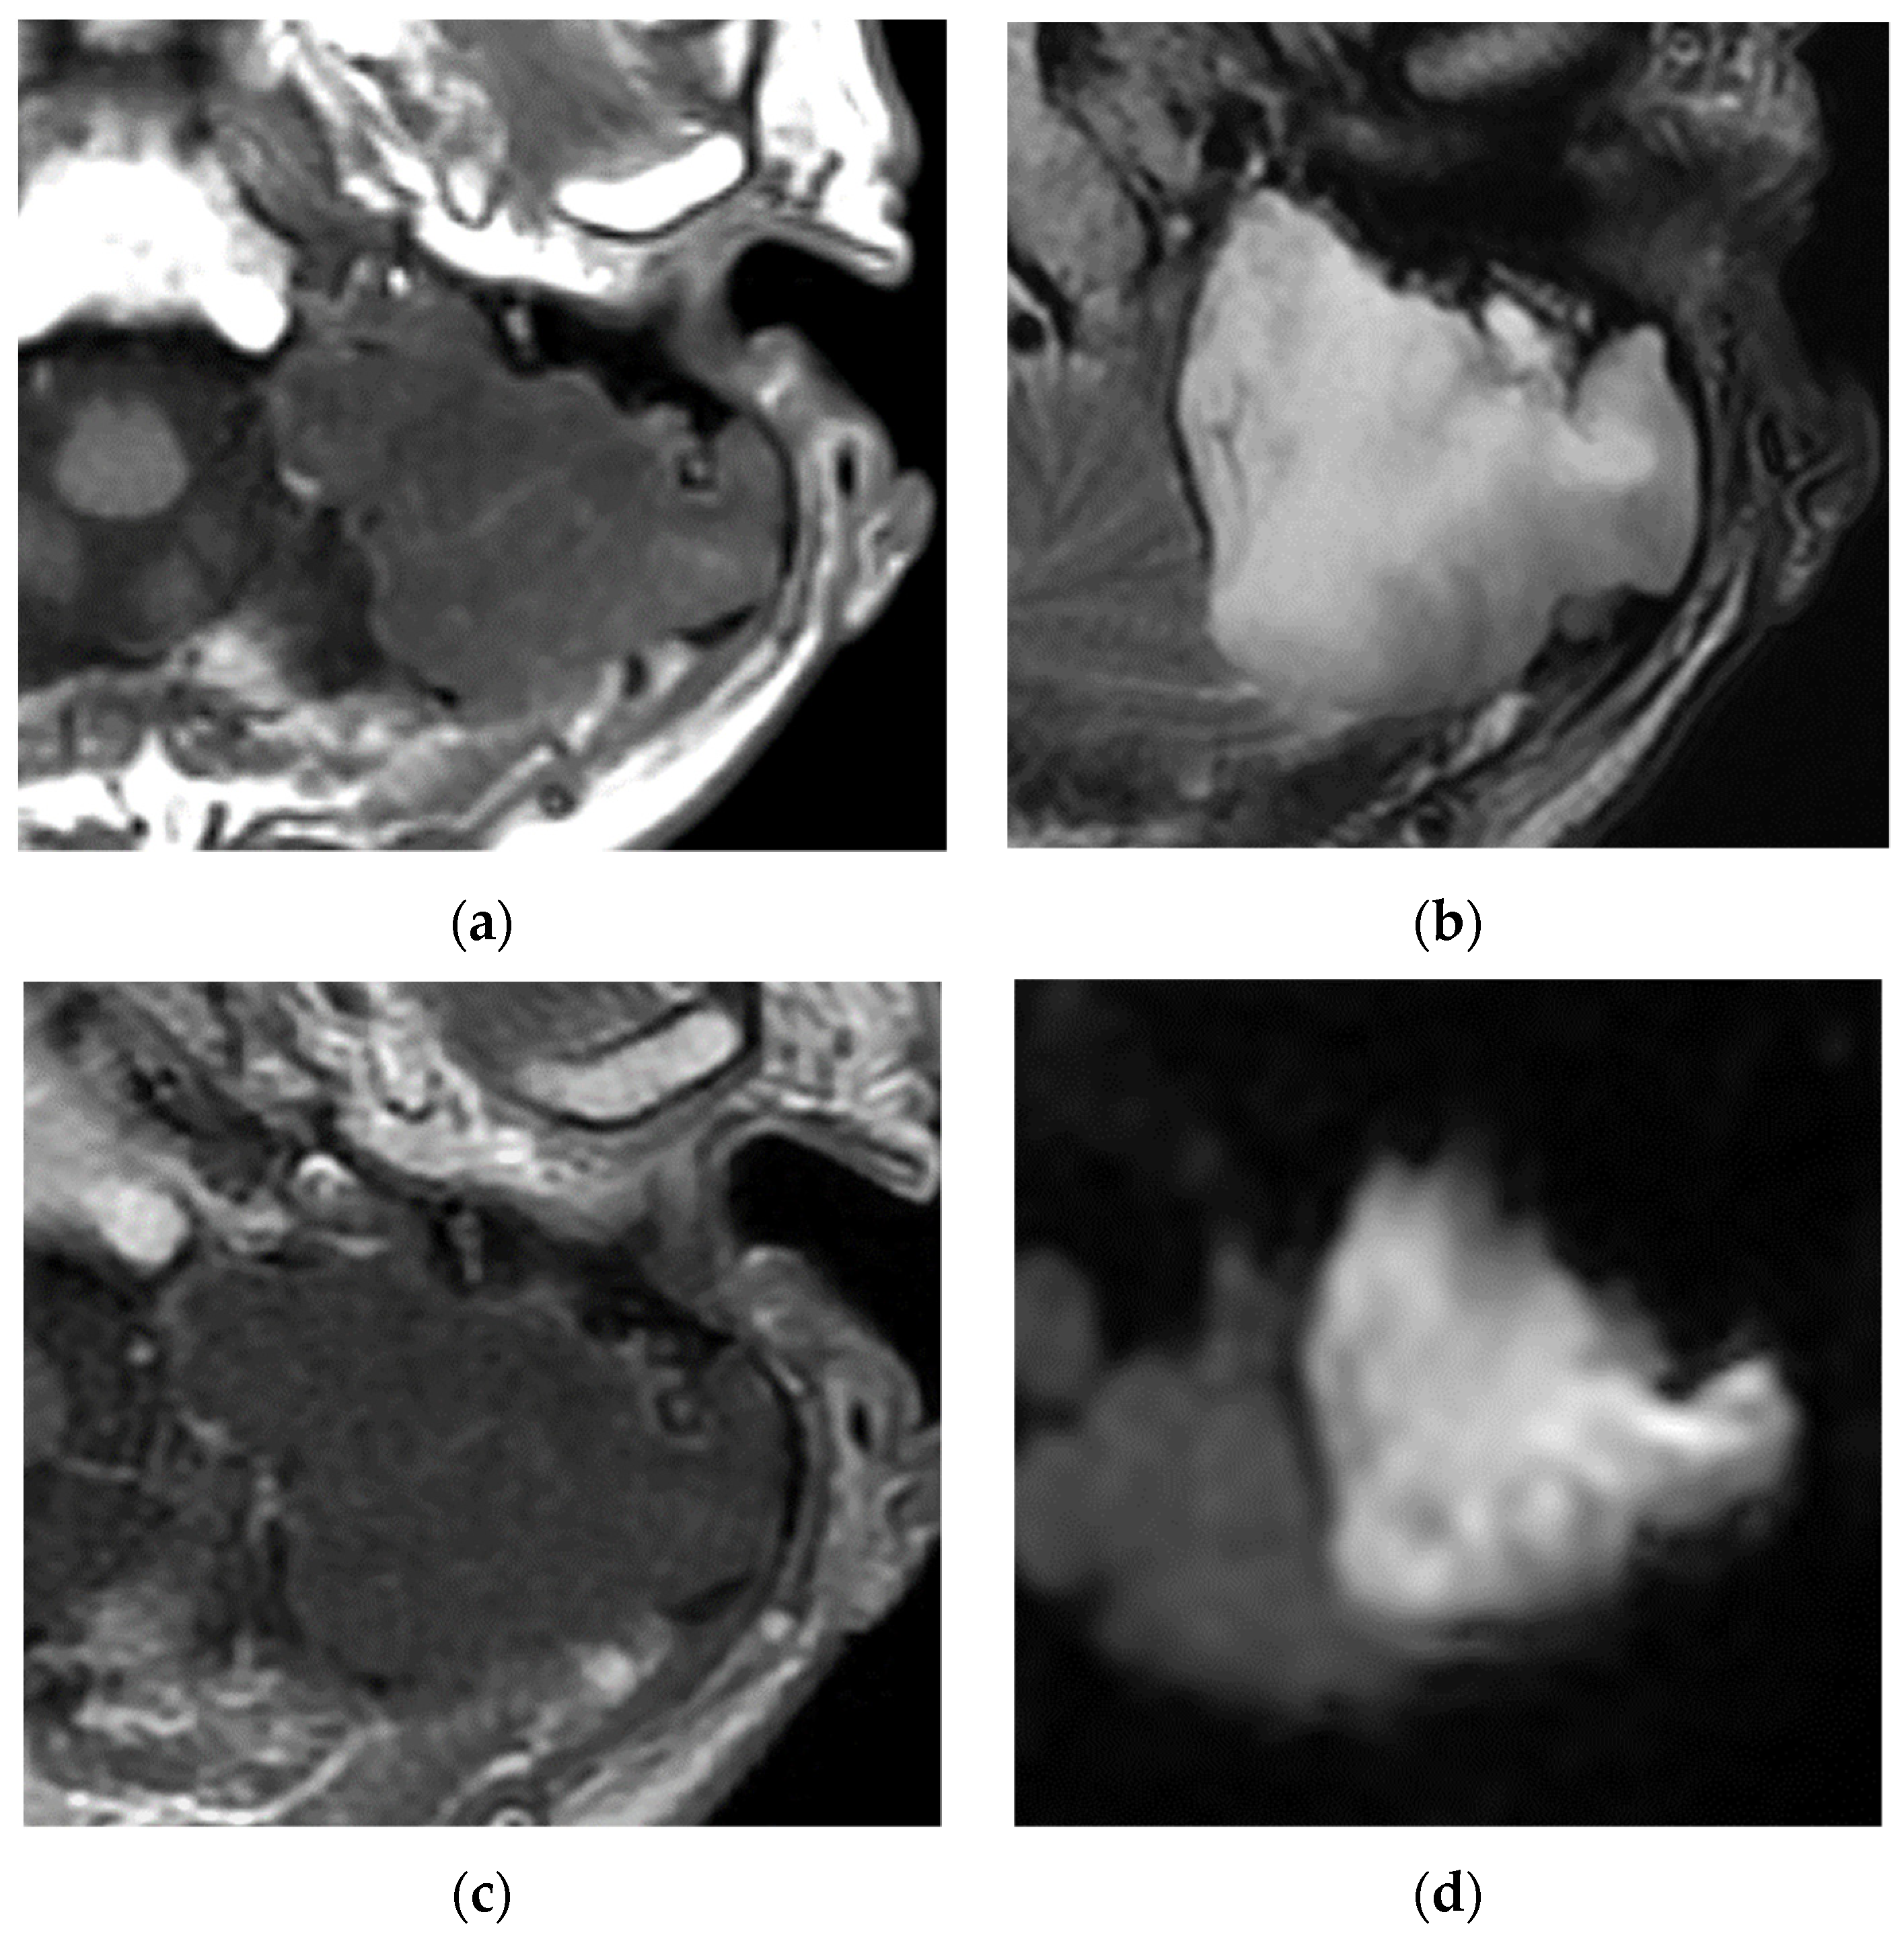

2.3. Around the Endolymphatic Sac